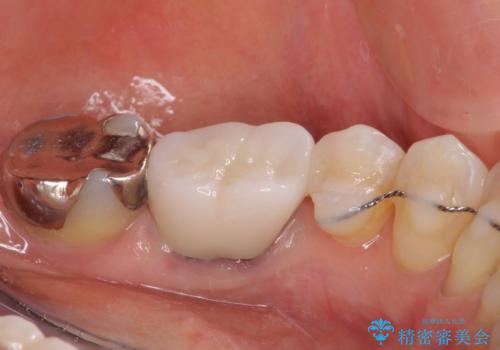

上唇小帯を切除したことで、ブリッジのダミー部分に触れて腫れていた歯肉は健全な状態になりました。

隙間もなくなったことで話す際の空気の漏れや、ものが挟まることもなくなりました。